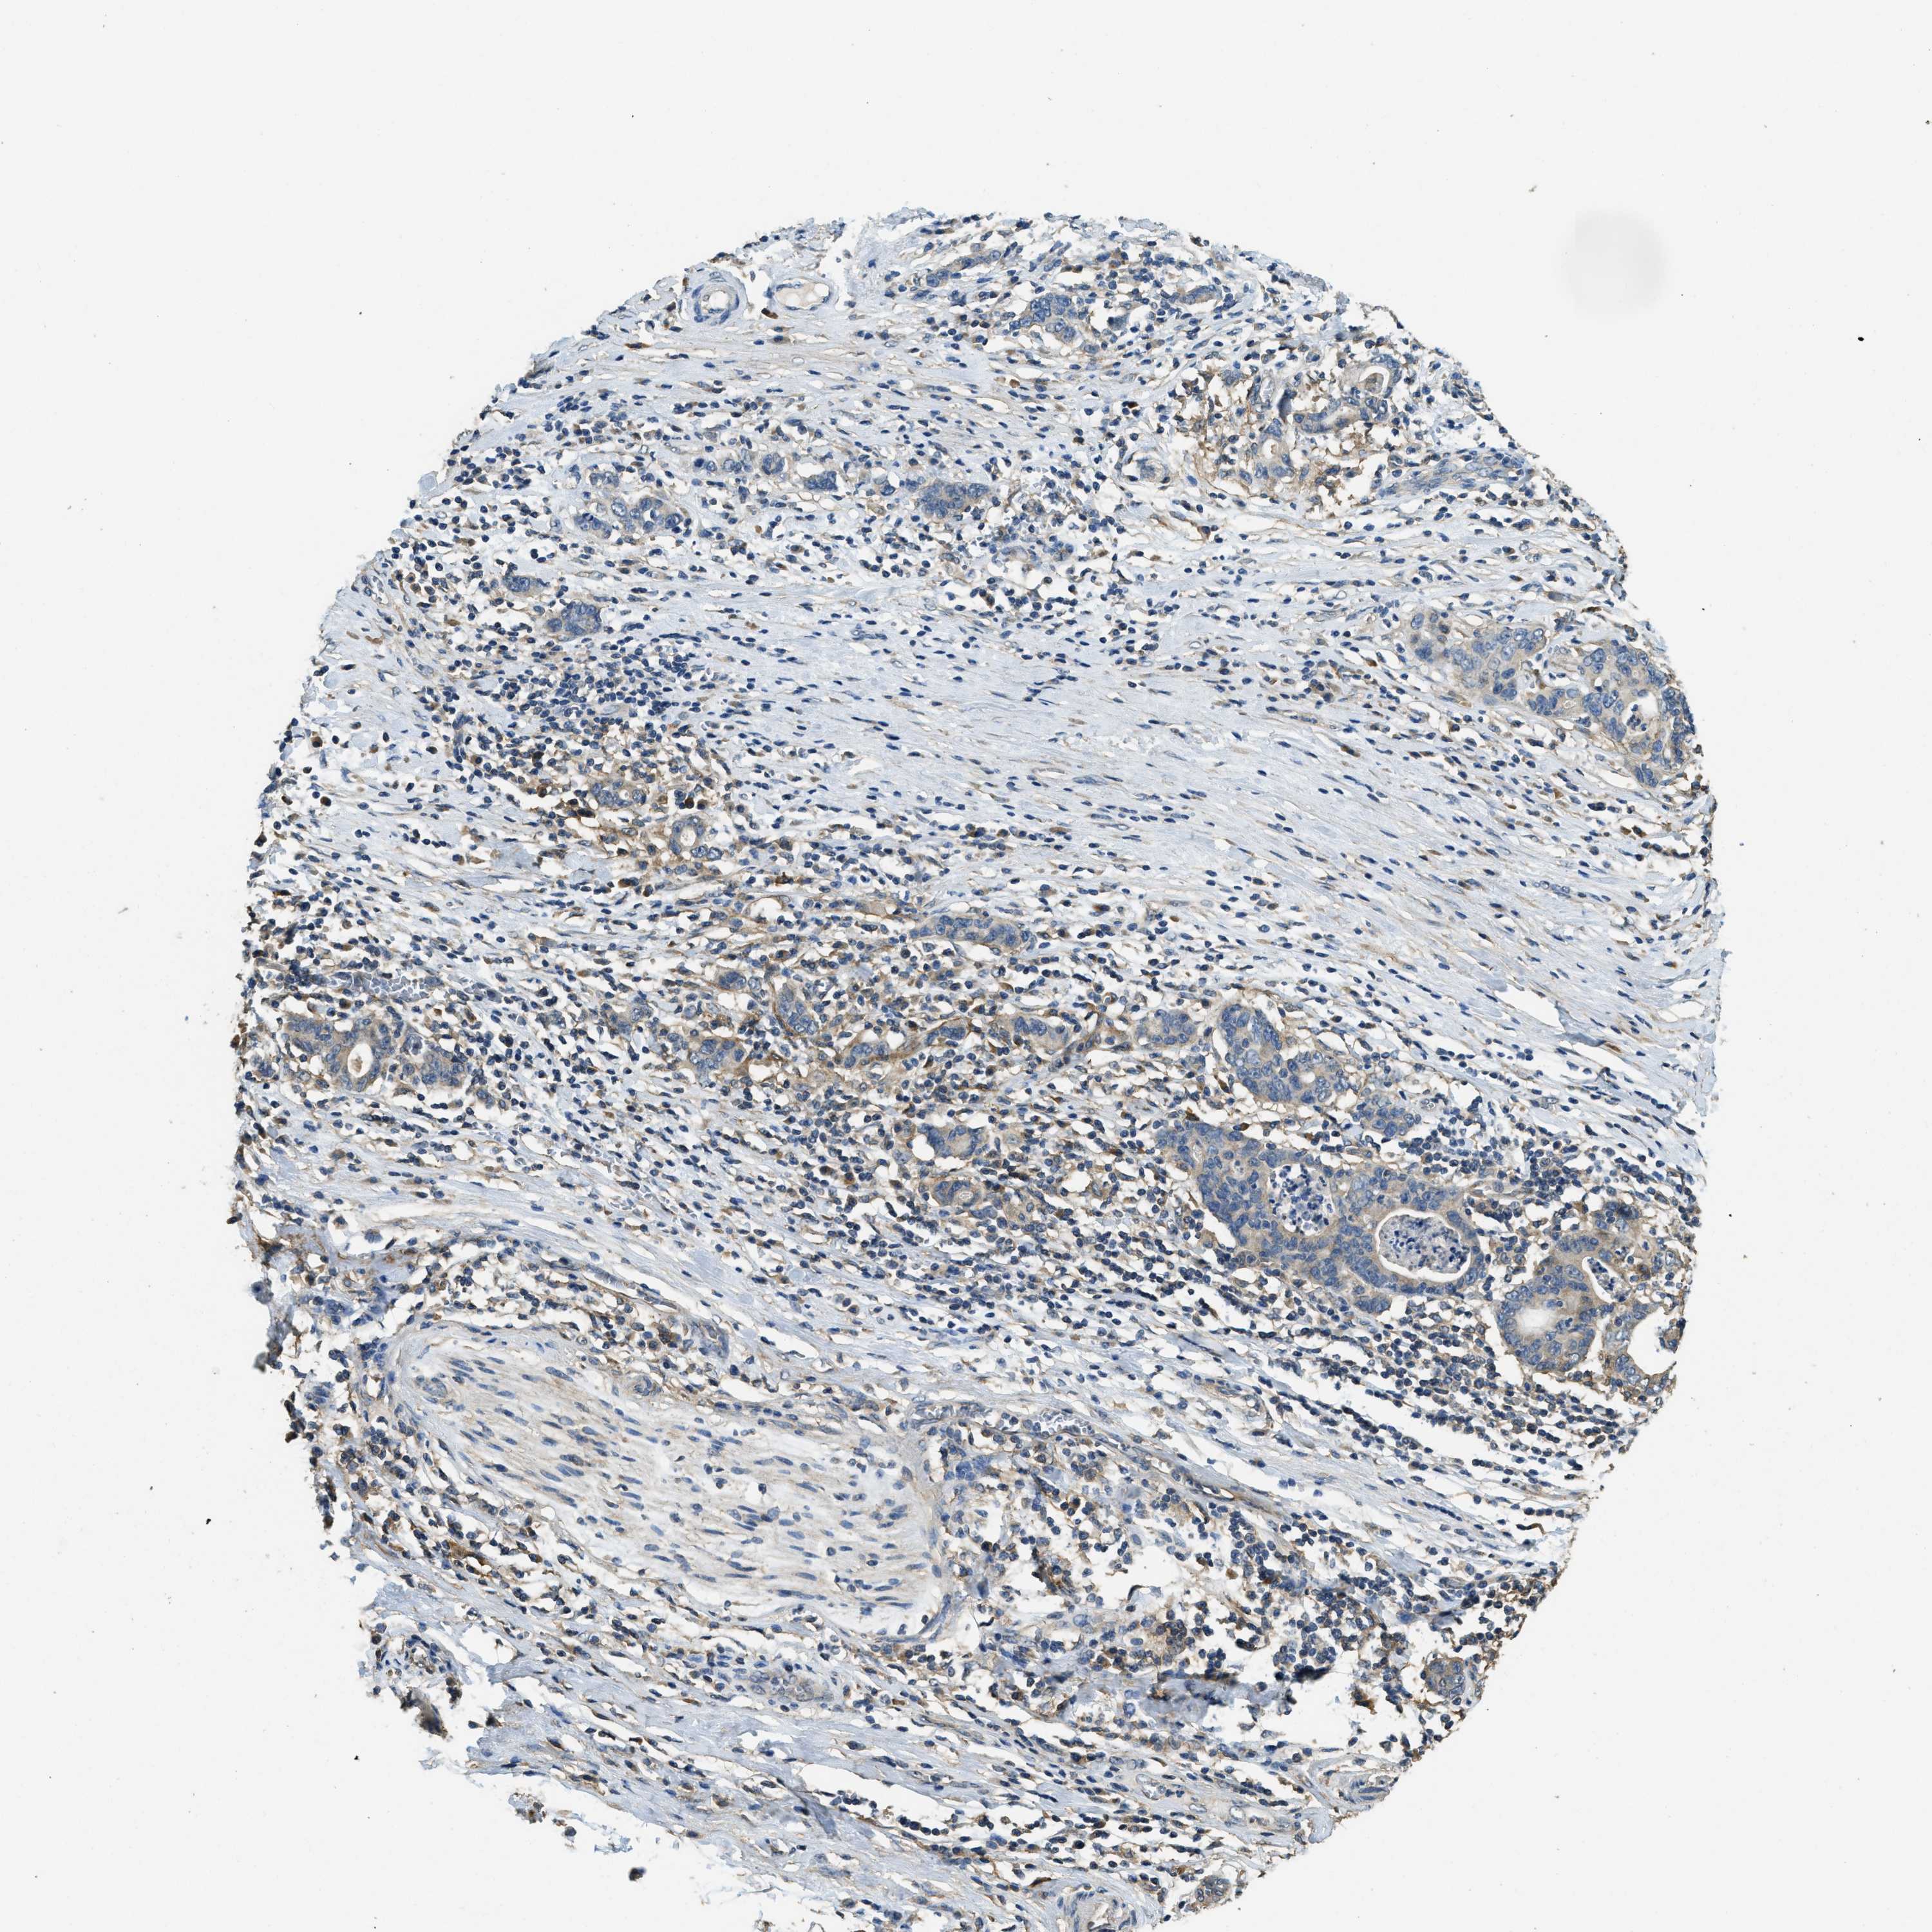

STOMACH CANCER - Protein expressioni

A mouse-over function shows sample information and annotation data. Click on an image to view it in a full screen mode. Samples can be filtered based on level of antibody staining by selecting one or several of the following categories: high, medium, low and not detected. The assay and annotation is described here.

Note that samples used for immunohistochemistry by the Human Protein Atlas do not correspond to samples in the TCGA dataset.

Antibody stainingi

Antibody staining in the annotated cell types in the current human tissue is reported as not detected, low, medium, or high, based on conventional immunohistochemistry profiling in selected tissues. This score is based on the combination of the staining intensity and fraction of stained cells.

Each image is clickable and will lead to virtual microscopy that enables deeper exploration of all samples and also displays staining intensity scores, fraction scores and subcellular localization as well as patient and tissue information for each sample.

Antibody HPA009285

Antibody HPA017139

Antibody CAB017826

Staining

High

Medium

Low

Not detected

Intensity

Strong

Moderate

Weak

Negative

Quantity

>75%

75%-25%

<25%

None

Location

Nuclear

Cytoplasmic/membranous

Cytoplasmic/membranous,nuclear

Adenocarcinoma, NOS

Adenocarcinoma, High grade